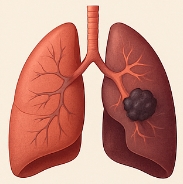

폐암 초기증상 중 가장 심각하게 봐야 할 것이 혈담입니다. 가래나 기침에 피가 섞여 나오는 경우는 폐 내부 혈관 손상과 관련이 있습니다. 객혈은 폐암 초기증상이 진행되고 있다는 강력한 신호이므로, 즉시 병원 진료가 필요합니다.